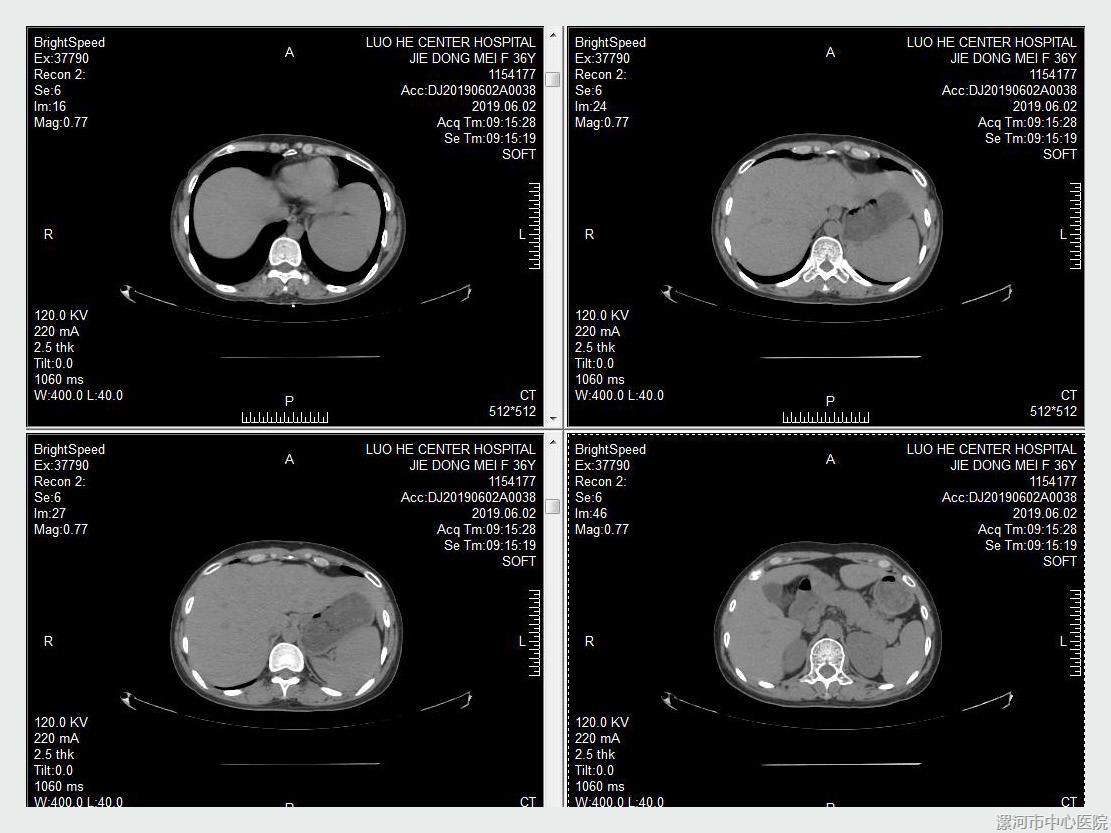

一位年轻女性患者于2018-2019年间间断因为肝功能异常入院,该患者曾经因皮肤病较长时间服用中成药物治疗,入院后经过询问病史及检查,初步诊断药物性肝损伤,停用该药物并给予保肝治疗,但治疗中发现转氨酶下降不理想,治疗中进一步检查发现患者免疫球蛋白较高,且抗核抗体较高,不排除自身免疫性肝炎存在,建议患者进行肝穿刺活检,最终患者完成肝穿刺活检术,活检病理提示自身免疫性肝炎可能,加用激素治疗后患者肝功能明显好转,后建议加用免疫抑制剂减少激素应用,出院后定期复查,患者一般情况稳定。